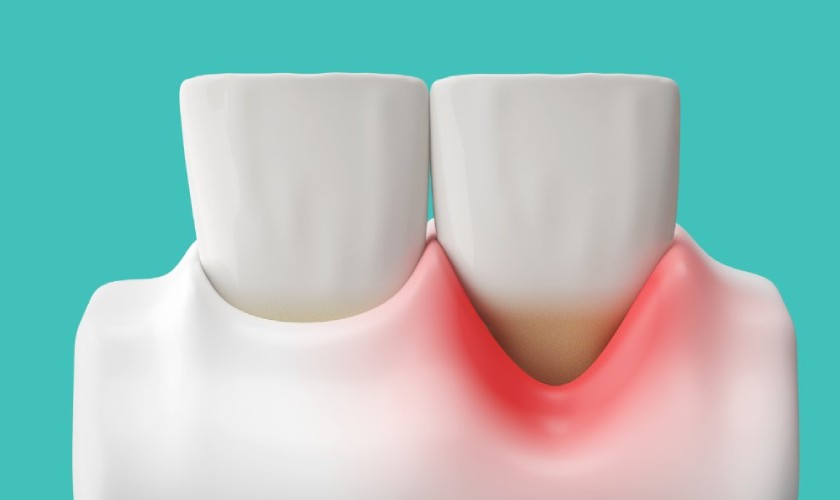

Túi nha chu là một khoảng trống hình thành giữa răng và nướu do sự phá hủy mô liên kết và xương nâng đỡ răng. Đây là một trong những dấu hiệu nghiêm trọng của viêm nha chu – bệnh lý ảnh hưởng trực tiếp đến sức khỏe răng miệng và có thể gây mất răng nếu không được điều trị kịp thời.

Khi vi khuẩn từ mảng bám tích tụ lâu ngày, chúng kích thích phản ứng viêm và làm tiêu xương ổ răng, khiến nướu tách khỏi bề mặt răng. Theo thời gian, túi nha chu ngày càng sâu hơn, tạo điều kiện cho vi khuẩn xâm nhập sâu hơn vào mô nướu và gây tổn thương nghiêm trọng.

Túi nha chu là một khoảng trống giữa răng và nướu, hình thành do mảng bám lâu ngày không được loại bỏ